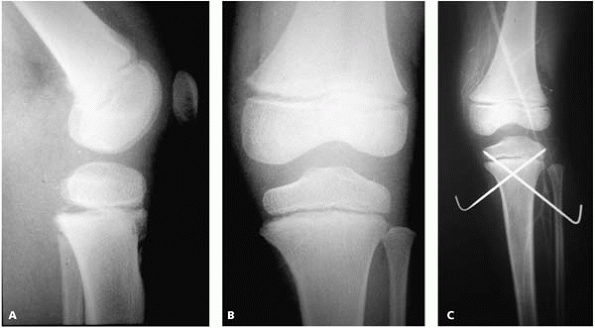

![]() |

▪ FIGURE 9-10 Child on back of bicycle struck by car sustained ipsilateral proximal femoral and tibial shaft fracture. A,B: proximal tibial physeal fracture on initial radiographs were not appreciated. C:

Following external fixation of the tibial diaphyseal fracture, a Salter-Harris Type I fracture of the proximal tibial physeal is evident. D: Closed reduction and K-wire fixation were used to treat the proximal tibial physeal fracture. E: Compartment syndrome occurred, which is associated with proximal physeal fractures of the tibia. In this case, the contribution of concomitant injuries to the compartment syndrome is difficult to discern. |